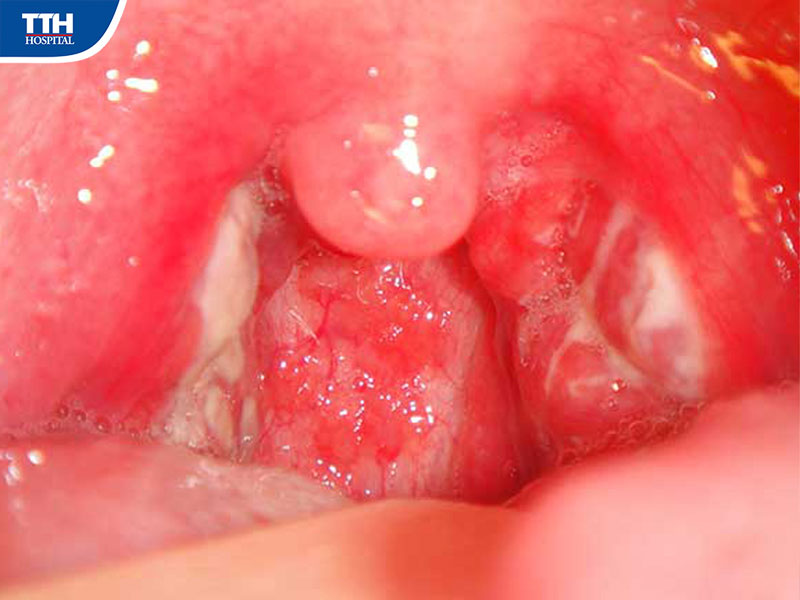

Viêm amidan mãn tính là gì?

Amidan là hai khối mô lympho nằm ở hai bên họng, có vai trò quan trọng trong việc bảo vệ cơ thể trước sự xâm nhập của vi khuẩn và virus qua đường hô hấp.

Khi amidan bị viêm nhiễm lặp đi lặp lại nhiều lần và kéo dài, tình trạng này có thể chuyển sang viêm amidan mãn tính. Lúc này, amidan không còn thực hiện tốt chức năng bảo vệ mà ngược lại còn trở thành ổ viêm nhiễm trong cơ thể.

Dấu hiệu viêm amidan mãn tính ở người trung niên

Viêm amidan mãn tính thường không biểu hiện rầm rộ như viêm cấp tính mà diễn ra âm thầm với các triệu chứng như: